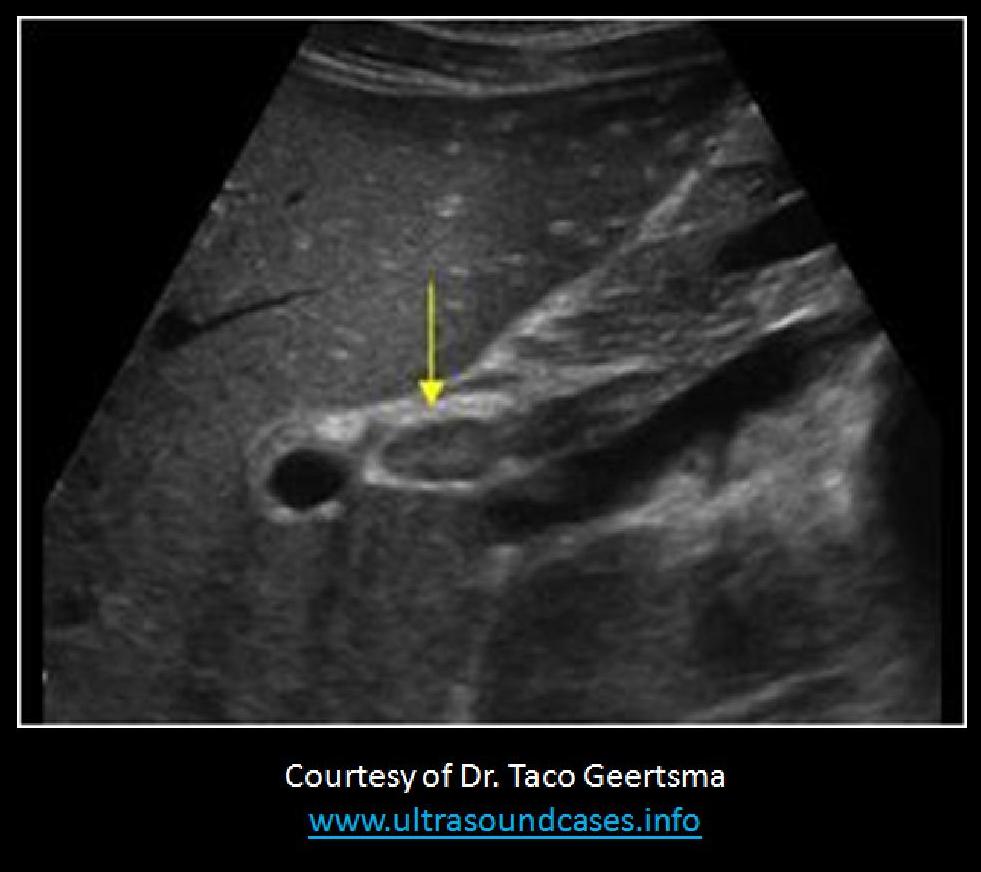

Which of the following statements correctly, describes the findings on the image?

The portal vein is measured correctly and demonstrates possible portal hypertension